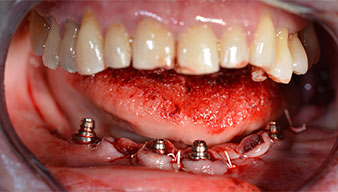

Angled abutments (35°) were screwed in to compensate for the divergence of the distal implants, with the result that the emergence profile of all implants was as perpendicular as possible to the bite plane. This is a prerequisite for occlusal placement of the provisional and subsequently the permanent denture (Fig. 15 and 16).

The impression and bite registration were then performed so that the dental technician could begin producing the provisional restoration immediately. This was then screwed in on the same day (Fig. 17 and 18).

The light increases the contrast in the oral cavity and improves visual perception. Both the contra-angle handpiece and the S-11 straight handpiece from W&H are externally cooled, which can be seen as a great advantage because the saline solution arrives exactly where it’s needed and can also be subsequently adjusted if necessary. The contra-angle and straight handpieces can be dismantled, which is highly recommended for hygiene and sterilizability. Four SKY implants measuring 4.0 x 14mm were placed.